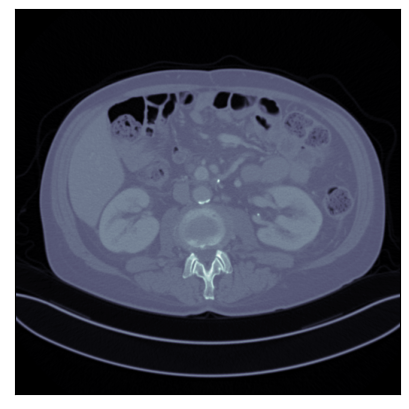

Refer to captionRefer to caption

Ground-truth

FBP: 21.303 dB, 0.195

TV: 31.690 dB, 0.889

U-Net: 36.712 dB, 0.920

LPD: 36.810 dB, 0.912

AR: 36.694 dB, 0.907

ACR: 35.708 dB, 0.897

ACNCR: 36.533 dB, 0.921

AWCR: 37.603 dB, 0.918

AWCR-PD: 37.941 dB, 0.924

Figure 2: Reconstructed images obtained using different methods, along with the associated PSNR and SSIM, for sparse view CT. In this case the AWCR and AWCR-PD achieve the highest PSNR and SSIM. Furthermore, both AWCR methods retain the fine-structure in the reconstruction, unlike the ACNCR and ACR, the only other methods which possess convergence guarantees.

These comparisons illustrate the trade-offs in levels of constraints and supervision versus stability and performance. For details of the experimental set-up, see Section G.1. We measure the performance in terms of the peak signal-to-noise ratio (PSNR) and the structural similarity index (SSIM) [Wang et al., 2004]. We report average test dataset results in Table 1, with further visual examples in Figure 2.

Sparse view CT As in [Lunz et al., 2018] performance of AR during reconstruction begins to deteriorate if the network is over-trained, so early stopping must be employed in training. For the ACR, ACNCR, and both AWCR methods this does not occur due to reduced expressivity, yet both AWCR methods surpass the performace of AR. Indeed, the AWCR-PD method approaches the PSNR accuracy of the strongly supervised U-Net post-processing method.